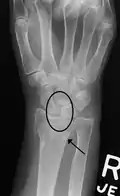

In order to diagnose a SLAC wrist you need a posterior anterior (PA) view X-ray, a lateral view X-ray and a fist view X-ray.[8] The fist X-ray is often made if there is no convincing Terry Thomas sign. A fist X-ray of a scapholunate ligament rupture will show a descending capitate bone. Making a fist will give pressure at the capitate, which will descend if there is a rupture in the scapholunate ligament.

Dynamic scapholunate instability visible upon clenching the wrist -

Scapholunate ligament disruption associated with a Colles' fracture